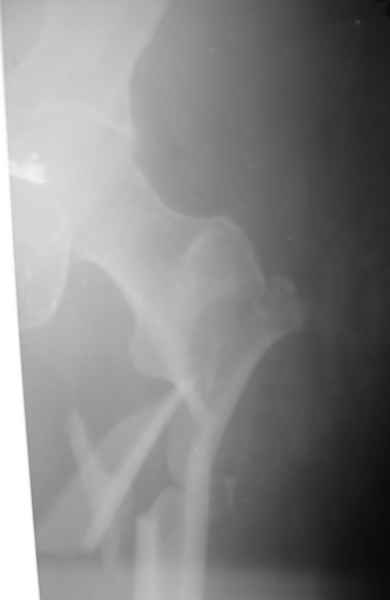

Уважаемые коллеги! Ваше мнение методов фиксации перломов бедер? Планирую: ретрограднный

БИОС в правое бедро. Реконсруктивный правый гвоздь на левое бедро. Конструкции ChM.